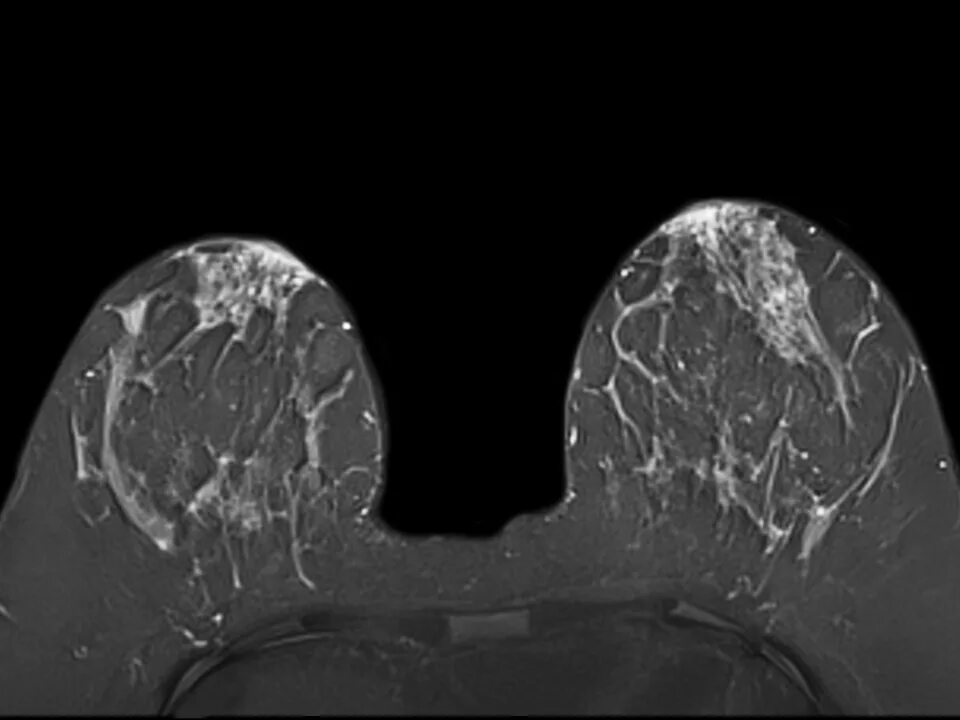

Как проводится мрт молочной железы